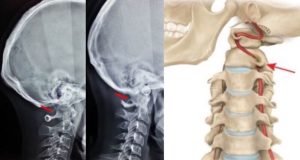

Головные боли после удара: когда нужна компьютерная томография

Головная боль после удара головой — распространённый симптом, который не стоит игнорировать. Даже если травма кажется незначительной, а общее состояние остаётся удовлетворительным, внутри черепа могут происходить опасные процессы. Особенность черепно-мозговых травм заключается в том, что некоторые осложнения развиваются постепенно и не всегда проявляются сразу. Именно поэтому при появлении головной боли после удара врачи часто рекомендуют […]

Как КТ помогает травматологам: неочевидные переломы, гематомы и повреждения

Компьютерная томография – это диагностический метод, широко применяемый в направлении травматологии для детальной визуализации прежде всего костных структур, а также мягких тканей, суставов и сосудов. С помощью такого исследования можно получить трехмерные снимки внутренних тканей для точного определения типа повреждения и выбора наиболее эффективной схемы лечения. Показаниями к проведению КТ являются: Подозрение на перелом конечностей […]